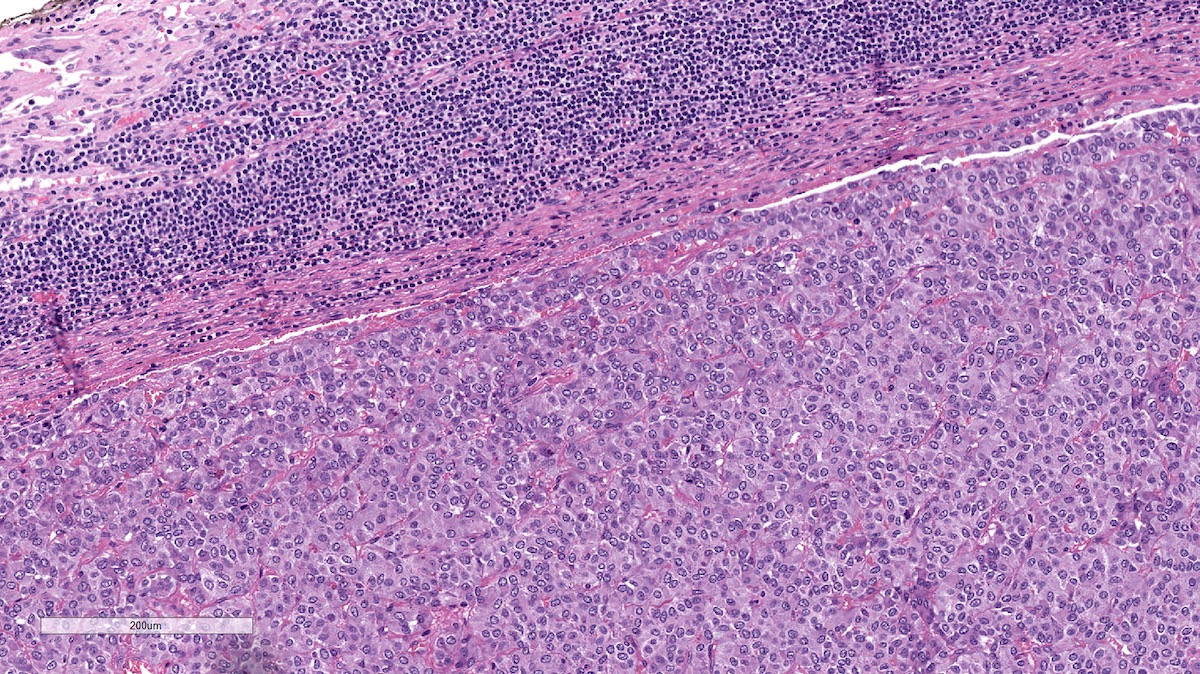

Microscopic (histologic) description

- Prevailing histologic pattern: epithelioid chief cells arranged in distinctive clusters / nests (zellballen pattern), separated by prominent fibrovascular stroma (J Clin Med 2018;7:280)

- Trabecular pattern: ribbons or cords of epithelioid cells divided by fibrous bands

- Other patterns: pseudorosette, angioma-like, spindled and sclerosing

- Chief cells: round, oval to polygonal cells with abundant granular basophilic, eosinophilic or amphophilic cytoplasm (Surg Pathol Clin 2019;12:951)

- Intracytoplasmic hyaline globules may be present in sympathoadrenal paragangliomas

- Giant multinucleated cells and bizarre cells can be present (Srp Arh Celok Lek 2002;130:7)

- Rarely, elongated and spindle shaped cells with a sarcomatoid appearance may be found

- Scattered ganglion cells can be seen

- May have nuclear atypia

- May have dysmorphic vessels, melanin-like pigment (neuromelanin) (pigmented paraganglioma), amyloid, abundant stroma and osseous metaplasia (Diagn Pathol 2012;7:77, Hum Pathol 1992;23:33)

- No or rare mitotic figures except in highly aggressive rapidly proliferating lesions

- May have focal chronic inflammatory infiltrate

- Necrosis is unusual except in patients who have undergone preoperative tumor embolization

- Special histopathologic features usually related to genetic syndromes:

- VHL syndrome: prominent stromal edema, clear cytoplasm and lipid degeneration (Am J Surg Pathol 1987;11:480)

- SDHx related syndrome: granular eosinophilic cytoplasm (Am J Surg Pathol 2020;44:422)

- MEN2 syndrome: unilateral or bilateral adrenal medullary hyperplasia (Neoplasia 2014;16:868)

Microscopic (histologic) images

Contributed by Luvy Delfin, M.D. and Sylvia L. Asa, M.D., Ph.D.